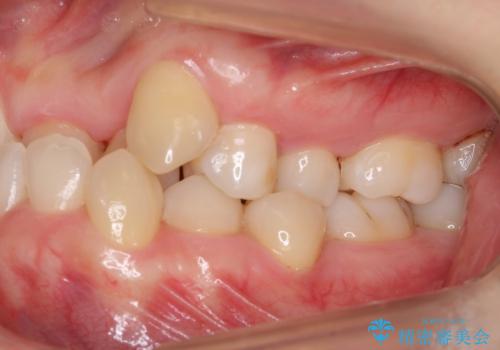

受け口 絶対に顎の手術はしたくない

- 受け口を主訴に来院。

下あごが大きく、顎の手術を含めた矯正をおすすめしましたが、手術は怖いので絶対にしたくないとのことでした。

かみしめもあり、骨も固く、歯根も長いためなかなか歯が動かず、患者様も治療する側も忍耐を要する長期戦となりました。